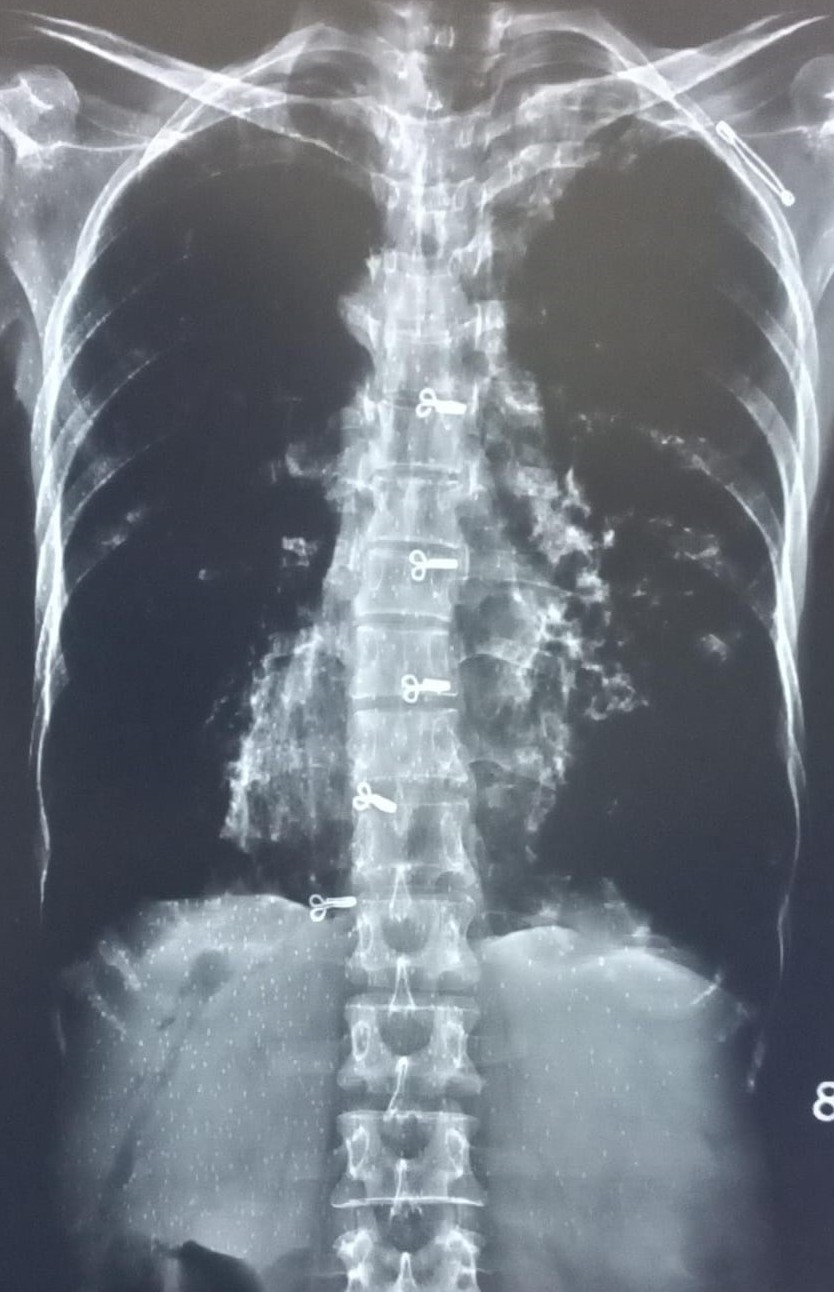

| 4437 | IGGMC, Nagpur, Nagpur | P2 | 29-35 | narendra parate | Consent taken on Paper | 25 Yrs. |

Provisional Diag : Cronic Cough

Final Diag : pleural effusion |

TB Case (Confirmed) | right CP angle blunted, suggestive of right sided pleural effusion | Abnormality visible on x-ray |